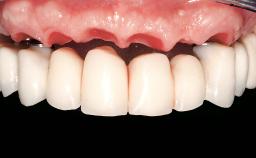

Immediate Loading of Six Implants in the Maxilla and Final Restoration with a Full-Arch Gold/Ceramic FDP Involving the Concept of Tilted Implants

A 61-year-old male patient with a failing fixed maxillary rehabilitation and a fixed mandibular rehabilitation requested a new fixed maxillary rehabilitation. The patient was wearing a temporary metal-reinforced maxillary bridge inserted two years before the consultation. He reported that his previous dentist did not want to insert a definitive framework because he considered the residual teeth to have a negative prognosis. The patient reported a history of recurrent caries and endodontic complications as the main reason for the previous extractions. The anamnesis was negative for periodontal disease and bruxism. The patient’s chief compliant was the mobility of his maxillary prosthesis, which needed to be re-cemented frequently, and discomfort during chewing.Moreover, the patient was not satisfied with the esthetic appearance of his maxillary teeth, which he found too long. The patient asked for a stable and comfortable fixed maxillary rehabilitation and firmly rejected any removable solution.

Prosthesis Type FDP

Defining Characteristics Fully edentulous upper jaw to be rehabilitated with an implant-borne fixed dental prosthesis

Esthetic Risk Medium